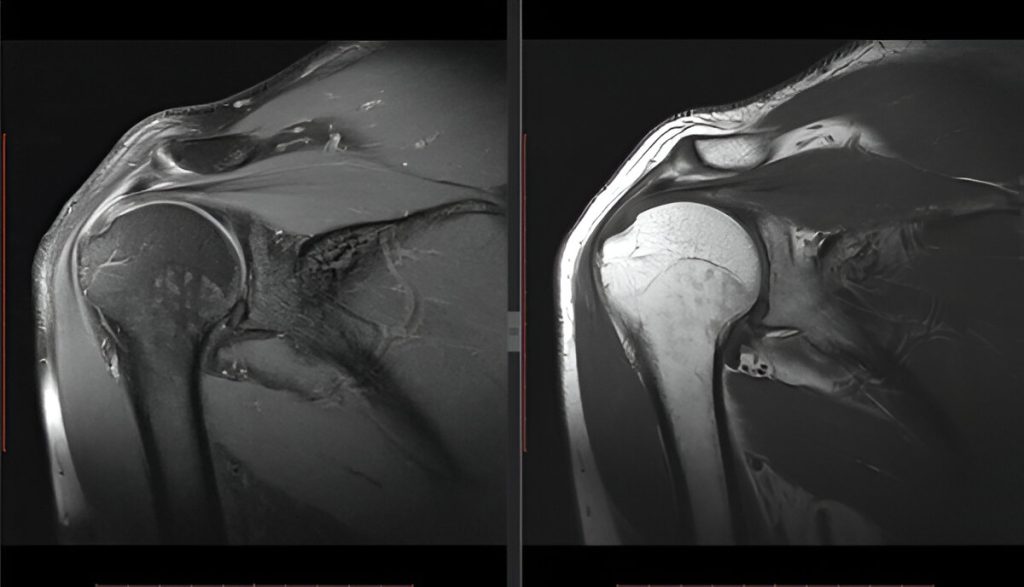

The Rotator Cuff: Stabilizers in Motion

The rotator cuff is a group of four muscles and tendons that stabilize the glenohumeral joint:

Supraspinatus

Infraspinatus

Teres minor

Subscapularis

These muscles keep the humeral head centered in the socket while allowing rotation and lifting.

Glenoid labrum – A ring of cartilage that deepens the socket for joint stability

Rotator cuff tears